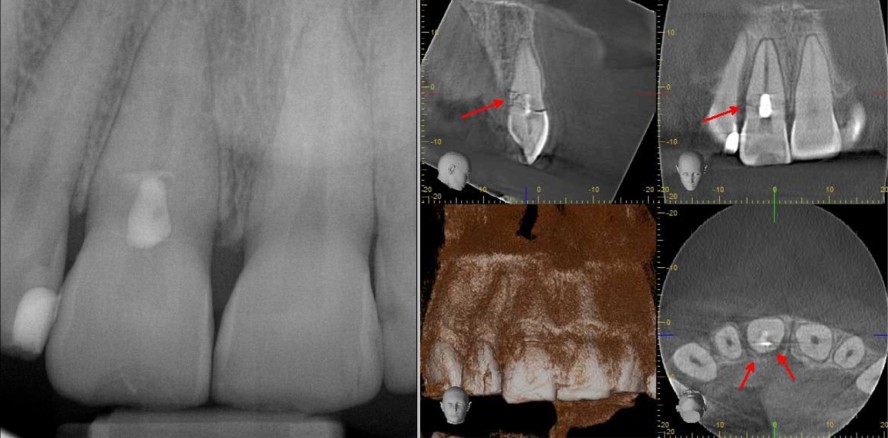

Lockerungsgrade, Reaktion auf Perkussion und Druck, je nach Untersuchungszeitpunkt auch Sensibilität auf Kälte (nicht sinnvoll am Unfalltag und kurz danach).Freiliegende Dentinareale sollten adhäsiv abgedeckt werden, falls nicht schon erfolgt.Wurde bei der Erstversorgung keine Bildgebung vorgenommen, sollten intraorale Einzel-Röntgenbilder erstellt werden. Je nach Schwere des Falles kann es unter Abwägung des Strahlenrisikos indiziert sein, ein DVT zu machen, insbesondere bei Verdacht auf Knochen- bzw. Wurzelfrakturen, da diese in zweidimensionalen Aufnahmen oft nicht ausreichend dargestellt werden können. (Abb. 1 und 2)

Ein Junge von neun Jahren wird beim Spielen mit dem Bruder von dessen Plastikschwert im Gesicht getroffen, es kommt zu einer komplizierten Kronen-Wurzelfraktur an Zahn 11 sowie einer unkomplizierten Kronenfraktur an Zahn 41. 41 wird mit einer Kunststoff-Füllung versorgt, bei 11 wird das Fragment (suboptimal) reponiert und eine partielle Pulpotomie durchgeführt. Strukturierte Nachuntersuchungen erfolgen in den nächsten zweieinhalb Jahren nicht, Schmerzen und Schwellungen führen schließlich zur Vorstellung in unserer Praxis. Die röntgenologische Untersuchung offenbart ausgedehnte Osteolysen an beiden Zähnen. Beide Zähne konnten mittels Wurzelkanalbehandlung therapiert werden, jedoch bleibt der langfristige Erhalt insbesondere von Zahn 11 abzuwarten, da nur über kieferorthopädische Extrusion und adhäsive Rekonstruktion des Zahnes die Frakturfolgen zu behandeln sein werden. (Abb. 6–10)